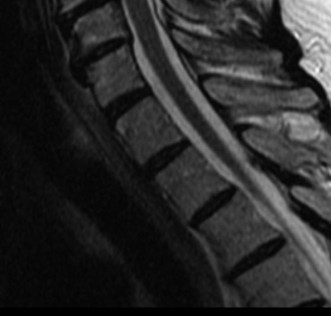

Determine the most appropriate treatment of different types of Hangman’s fractures? CASE 14 A 70-year-old retired, funeral director presents with symptoms of right upper extremity numbness and weakness. He reports that he developed acute neck and right upper arm pain while undergoing a dental procedure. Treatment so far has been nonsteroidal anti-inflammatory medication and physical therapy with cervical traction. While his pain improved with this course of treatment, he has ongoing paresthesias radiating into his right hand and weakness affecting his right upper extremity. Figures 1–20 and 1–21 show a midsagittal and axial image through C6–7, respectively.

The correct answer is (A). Considering the patient’s complaints and the imaging, he most likely has radiculopathy, probably secondary to a disc-osteophyte complex associated with foraminal stenosis at the C6–7 level. There is no suggestion in the history of walking imbalance or dexterity issues in the upper extremities. Thus, a diagnosis of myelopathy is less likely. Furthermore, the degree of spinal compression is mild and not likely (though not impossible) to cause spinal cord dysfunction. An intradural tumor would have a different MRI appearance, likely demonstrating an area of high signal within the parenchymal tissue of the spinal cord itself. A central cord syndrome is an acute spinal cord injury with upper extremities being affected more than lower extremities.

The correct answer is (C). The patient has nerve root compression at the C6–7 level, which would affect the exiting C7 nerve. Weakness of right elbow extension and wrist flexion with sensory loss of the middle finger are the most likely findings.

The correct answer is (D). The sagittal T2-weighted MRI demonstrates a relatively lordotic spine with multilevel degeneration and cord compression at C3–4, C4–5, and C5–6. There is both anterior and posterior effacement of the CSF. Anterior or posterior procedures might be appropriate. Of note, a posterior procedure, such as laminectomy and fusion or laminoplasty is a reasonable option because of the preserved lordosis. In fact, it has been suggested that either procedure can be performed in a cervical spine with no more than 13 degrees of kyphosis. Effective posterior decompression relies on directly removing the posterior compressive structures (i.e., infolded ligamentum flavum, facet joints) and indirect decompression from the anterior structures (i.e., discs, vertebral body osteophytes) via the spinal cord drifting posteriorly. In this specific case, of the choices, laminectomy and fusion of C2–6 would decompress the stenotic segments. A laminectomy of C3–6 might achieve adequate decompression, but it is not recommended to perform a laminectomy alone as it may result in post-laminectomy kyphosis. An anterior cervical discetomy and fusion (ACDF) might be appropriate, but choice B does not include the most stenotic level, C3–4. Likewise, a corpectomy can be appropriate, but choice C does not include the most stenotic level.